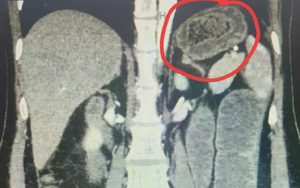

Qua thăm khám ban đầu, bệnh nhân được chỉ định siêu âm ổ bụng và phát hiện có ổ áp-xe gan. Khi tiến hành siêu âm kỹ hơn, ê kíp phát hiện một dị vật cản quang xuyên trong nhu mô gan, chiều dài ước tính khoảng 6-7cm. Ngay sau đó, bệnh nhân được chỉ định chụp cắt lớp vi tính (CT scan) ổ bụng. Kết quả cho thấy có một dị vật dạng que dài nằm hoàn toàn trong nhu mô gan, kèo theo ổ áp xe sâu. Trước nguy cơ biến chứng nặng nếu không điều kịp thời, ê kíp khoa Nội tiêu hóa đã nhanh chóng hội chẩn cùng khoa Ngoại Gan Mật Tụy, thống nhất phương án phẫu thuật lấy dị vật, dẫn lưu ổ áp xe, kết hợp điều trị kháng sinh phù hợp.

Hình ảnh CT Scan ổ bụng của bệnh nhân. Ảnh: BVCC.